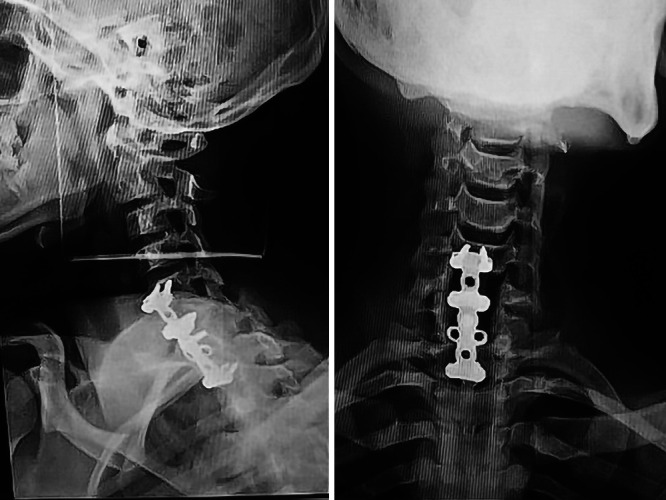

FIG. 3.

Postoperative radiographs.

Then the patient was placed supine, and an anterior approach was performed. A second attempt at intraoperative reduction either by traction or by Caspar retractor did not allow slight mobility of the spine. Thus, a C6 and C7 corporectomy was done with an iliac bone graft and C5–T1 plate fixation (Fig. 3). After 10 hours, the surgical procedure from the beginning of the posterior approach to the end of the anterior approach was completed. The postoperative period was uneventful, and frank improvement was noticed. Dysphagia and dysphonia disappeared within 2 days, which made us suspect that these symptoms occurred as the result of tracheal and esophageal compression by the dislocated cervical spine beyond C7, and muscular strength increased to 3/5 during the first week. The patient was discharged at hospital day 10 and was referred to the physical therapy department. At the 12-month follow-up, the patient was able to stand up without support and to walk but with obvious disbalance (Video 1). After 18 months, he had an ASIA grade E and was able to walk without any support. His gait was still normal 3 years postoperatively, with mild spasticity (Video 2).